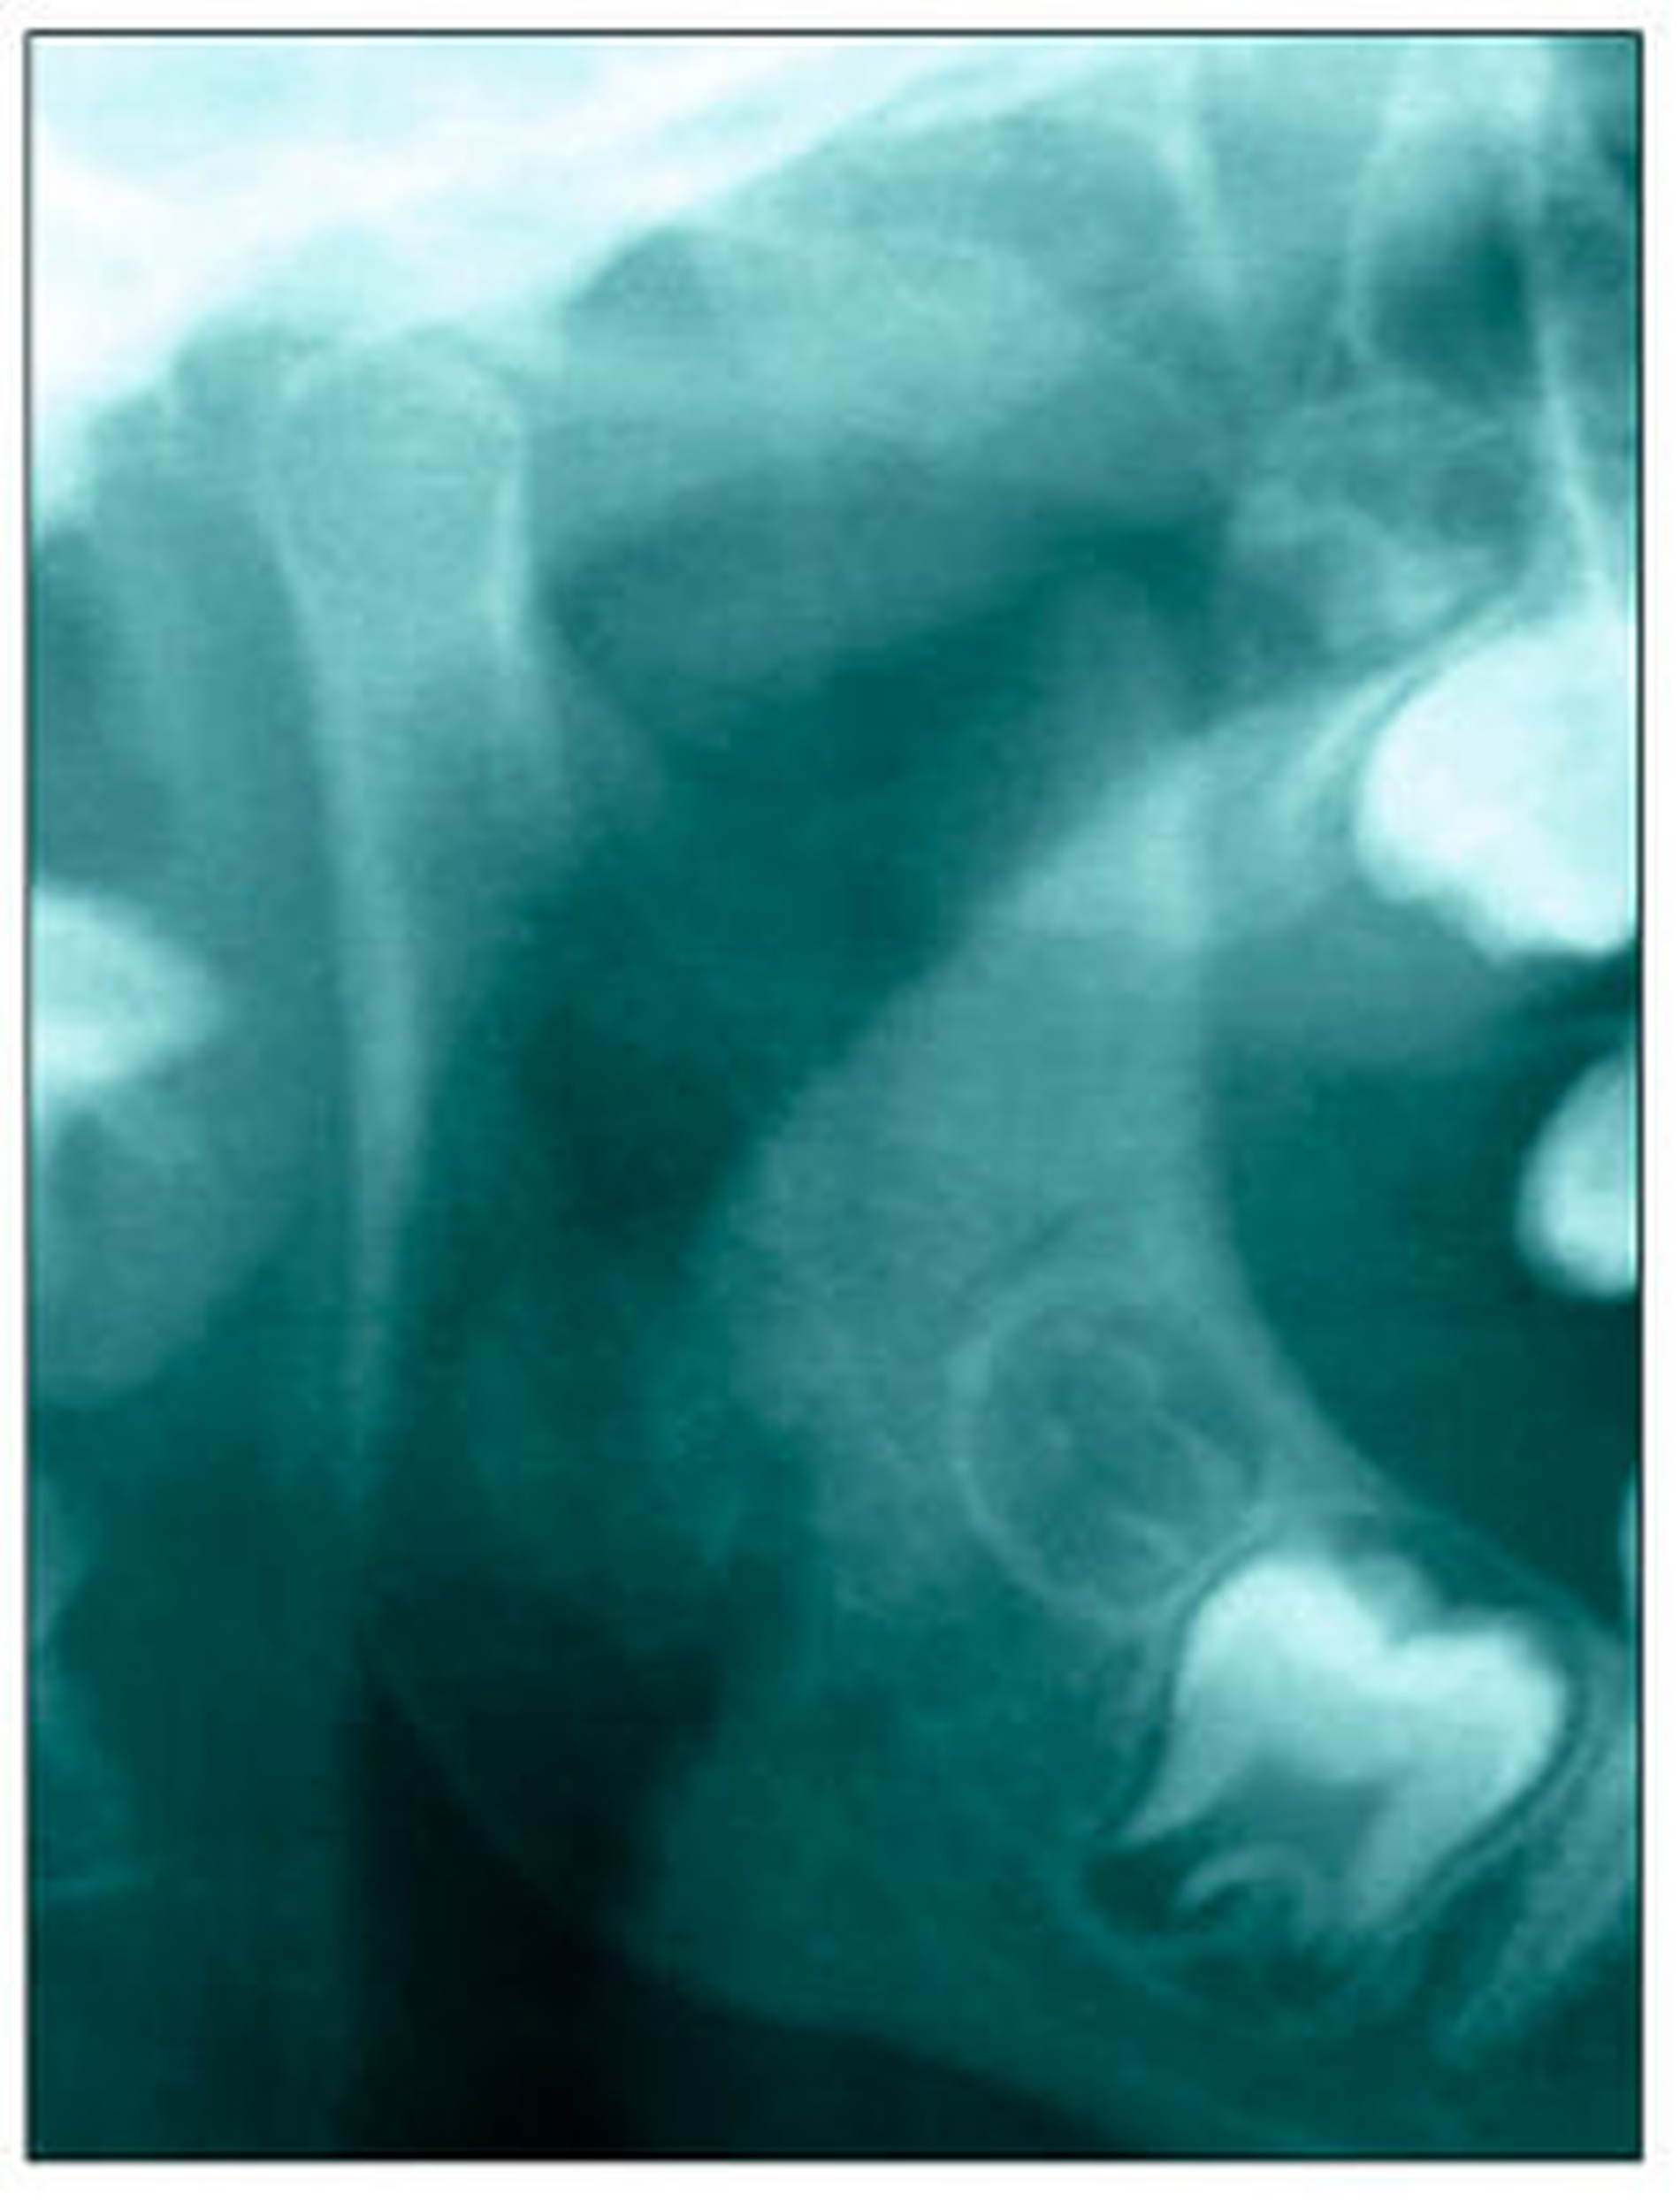

Bereits 2004 wies Carla Evans [Evans, 2005] auf das Risikomanagement bei Allgemeinerkrankungen hin und stellte am Beispiel der JIA dar, dass Unterkieferrücklagen und frontal offene Bisse aus der Kiefergelenkzerstörung entstehen können. Die Röntgenaufnahmen einer JIA-Patientin mit oligoartikulärer Form und Beteiligung des rechten Kiefergelenkes zeigen den typischen Verlauf sehr gut. Bei ursprünglich sehr dezenten Befunden, wie einer s-förmigen Mundöffnung von 44 mm, einer geringen Mittenabweichung um 2 mm nach rechts und einem frontal offenem Biss klagte sie über Schmerzen beim Essen, was den Anlass zur weiteren Diagnostik bot. Die erste Panoramaröntgenschichtaufnahme (Abbildung 1a-c) zeigt auf der rechten Seite einen abgeflachten Kondylus und eine bereits verstrichene Fossa condylaris. Ein Jahr später vermittelt das Fernröntgenseitenbild (Abbildung 1d) trotz fortschreitender kondylärer Resorption ein harmonisches Bild, während nach drei Jahren bei voranschreitendem Abbau des rechten Kondylus (Abbildung 1e) eine Rücklage der Mandibula und eine Bissöffnung manifest sind (Abbildung 1f).

Bei 152 durchschnittlich 12-jährigen Rheumapatienten wurden die kondyläre Morphologie und Symmetrie beziehungsweise Asymmetrie im Vergleich zu einer Kontrollgruppe anhand der OPG analysiert. Zur Analyse erfolgte die Zuordnung zu vier morphologischen Graden je Kondylus (Abbildung 3a-d). Bei 45 Prozent der Rheumapatienten waren morphologische Veränderungen im Rahmen kondylärer Resorption unterschiedlicher Ausprägung zu finden. Die „Kontrollpatienten“ ohne JIA zeigten nur zu 14 Prozent formatypische Kondylen. Der Unterschied zwischen den beiden Gruppen war signifikant. Daher sollte bei der Routineauswertung von Panoramaröntgenschichtaufnahmen auf diese Anzeichen geachtet werden, insbesondere auch unter dem Aspekt, dass laut Assaf [2011] durchschnittlich 4,3 Jahre zwischen Erstmanifestation der JIA und Erstvorstellung in der Rheumasprechstunde des UKE liegen.